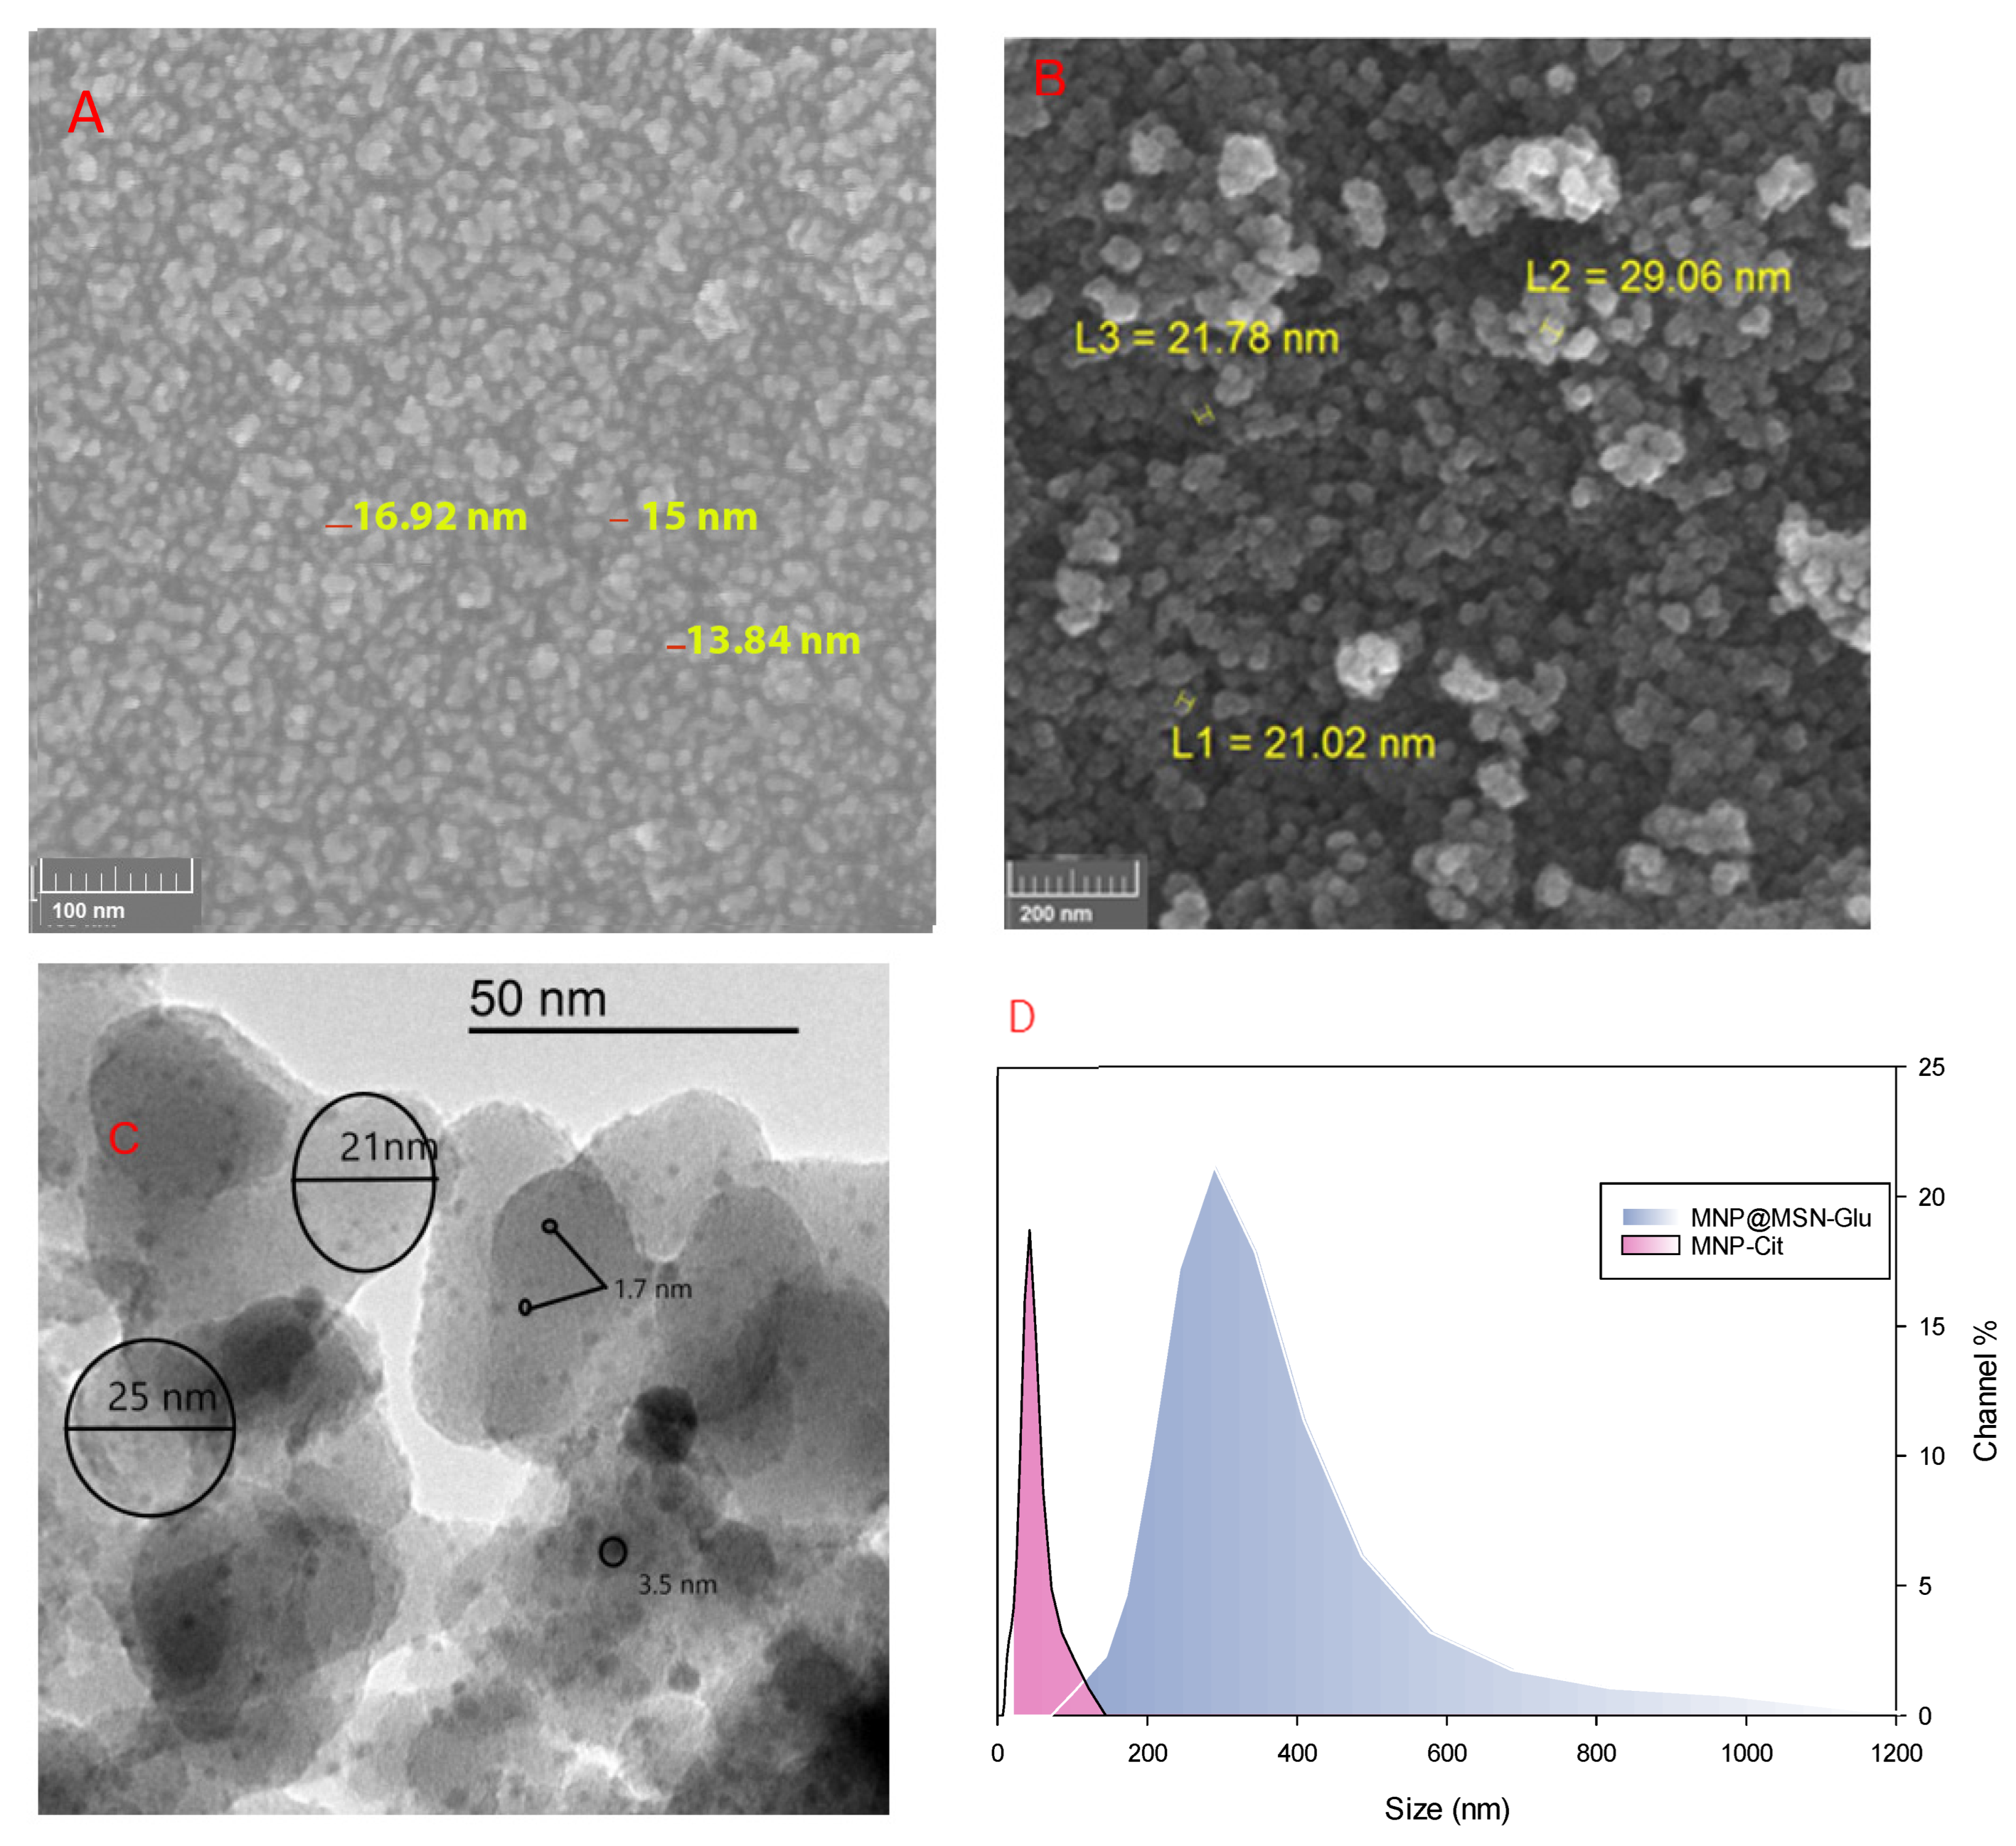

3.1. Synthesis and Characterization of MNP@MSN-MTX